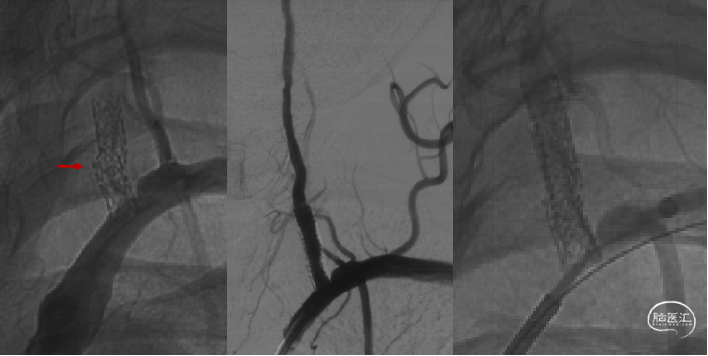

药物涂层球扩支架

63岁男性,“反复发作头晕、站立不稳3月”;定位准确、球扩时无移位。